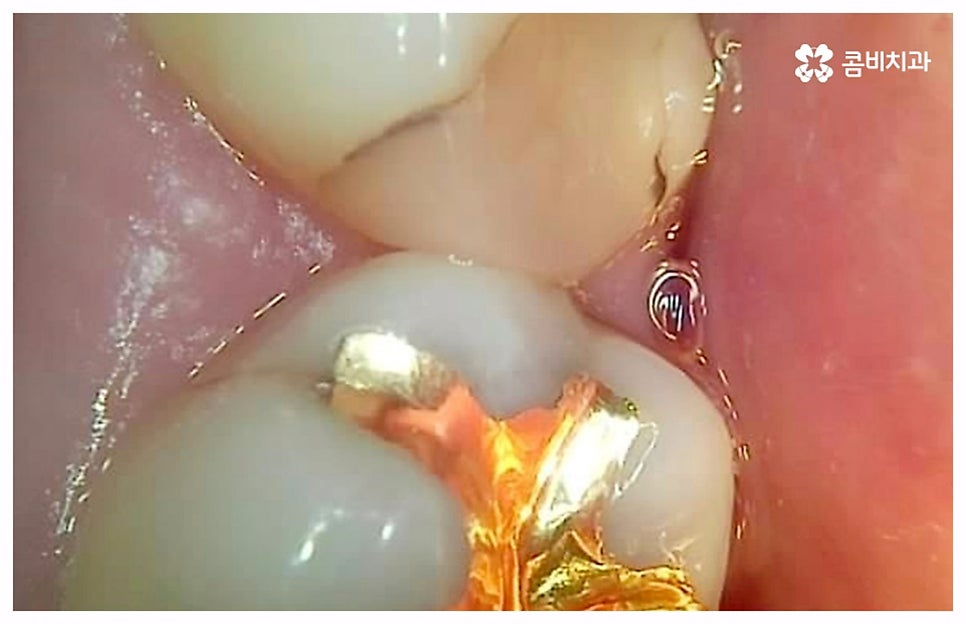

급성치수염에 대한 치료는 보통 안쪽까지 침투한 세균을 깨끗하게 긁어내고 염증 및 괴사된 치수 부분을 삭제한 다음 뿌리관(근관)을 소독하고 치과 충전물로 밀봉하는 신경 치료를 통해 이루어지는데, 이렇게 신경 치료를 진행하고 나서 후속 치료로서 남아있는 자연 치아를 보호하고 저작 기능을 제대로 수행할 수 있도록 하기 위해 주변 치아와 크기, 높이 등을 맞추어 딱 맞게 제작한 보철물을 덮어씌우는 크라운 치료를 해 주는 것이 자연 치아를 보다 오랜기간 동안 건강하게 사용할 수 있도록 하는데 크게 도움이 된다고 할 수 있어요. 경우에 따라서 앞니의 경우 신경관이 많지 않기 때문에 레진으로 치료를 마무리하는 경우도 있으니 참고해 주시면 좋을 것 같아요.

이 때 신경 치료가 끝나면 보통 통증이 사라지기 때문에 추후 시간적인 부분, 금전적인 이유 등 여러 가지 사정들로 인해서 크라운 치료가 필수적이지 않으면 신경 치료만 받고 끝마쳐도 되는지 문의를 주시는 분들이 있는데요. 크라운 치료를 해 준 치아의 경우 밀봉만 한 치아 보다 훨씬 수명이 길기 때문에 환자분들께서 크라운 치료의 필요성에 대해서 잘 인지하실 필요가 있어요. 이것은 신경 치료를 받은 치과 환자 4만 6000명을 분석한 미국 연구팀의 발표를 통해서도 알 수 있는데요. 이에 따르면 근관 속의 손상된 치수를 긁어내고 소독한 뒤 충전물로 밀봉한 치아의 경우 평균 생존 기간이 11.1년이었던 것에 반해서 추후 크라운까지 씌운 치아의 평균 수명은 약 20년으로 길어졌다고 하니 의료진과 충분히 상담하셔서 자신의 상황에 잘 맞는 보철물로 크라운 치료까지 끝마치시길 권유드리고 있습니다.